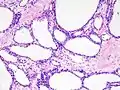

![]() | |

Micrograph showing a pancreatic serous cystadenoma. H&E stain. | |

Pathologists classify serous cystic neoplasms into two broad groups. Those that are benign, that have not spread to other organs, are designated "serous cystadenoma".[5] Serous cystadenomas can be further sub-typed into microcystic, oligocystic (or macrocystic), solid, mixed serous-endocrine neoplasm, and VHL-associated serous cystic neoplasm. This latter classification scheme is useful because it highlights the range of appearances and the clinical associations of these neoplasms. Serous cystic neoplasms that have spread ("metastasized") to another organ are considered malignant and are designated "serous cystadenocarcinoma".

Pathology